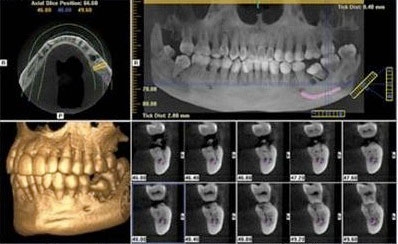

CBCT –Aplicatii in stomatologie

2.Computerul tomograf-conventional CT-cone beam CT.

5.Analiza3D

6.Cazuistica

1.Captarea unuivolum3D

2.Prelucrarea unui volum 3D –masuratori

3.Simulare implant